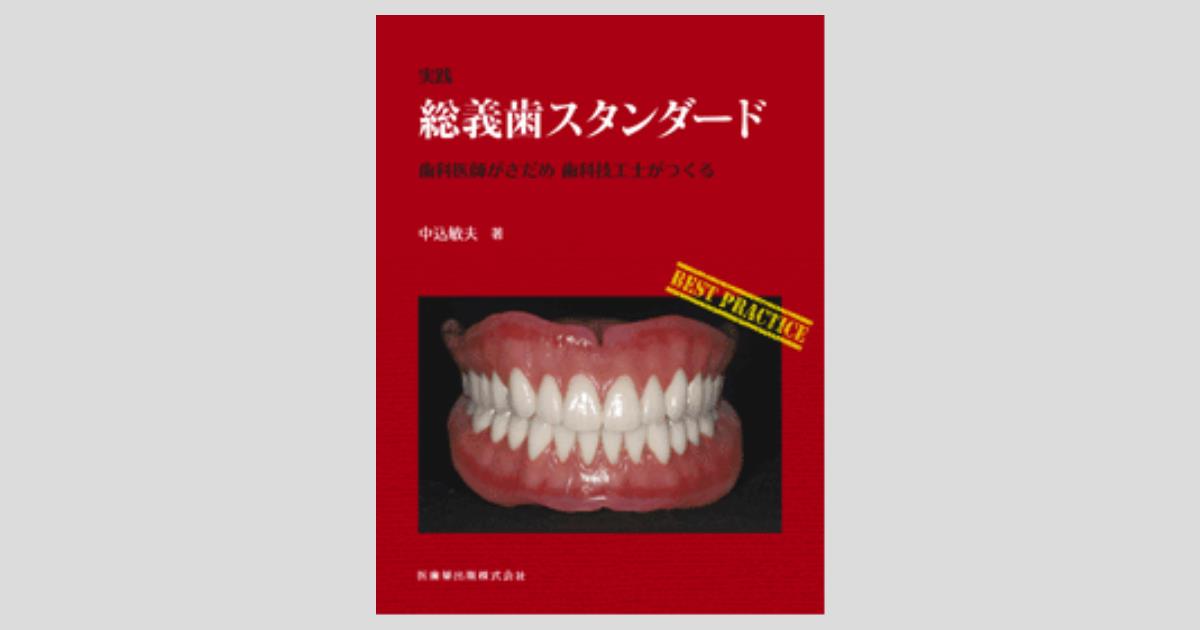

hqdefault.jpg。神戸市垂水区で「噛める入れ歯/専門・名医」|あかまつ歯科。入れ歯の治療について|下丸子で技工士在籍の歯医者。学生時代に制作したものです。上顎の前歯に欠けたところがあります。。実践総義歯スタンダード 歯科医師がさだめ 歯科技工士がつくる。フルデンチャーの上下とパーシャルデンチャーの上のみです。こうの早苗 バック キット。タフティングガン AK-1 カットパイル オレンジ。患者様への説明やサンプル等にご利用いただけると思います。値下げ 鼻-27【蒼海紋 ラリマー】13.6㍉玉